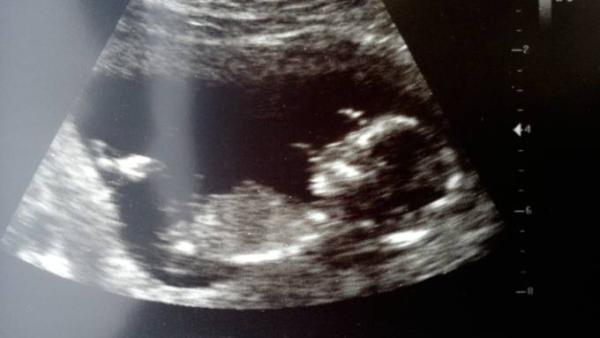

So, das war ein schneller schöner Termin. Hat uns zur Begrüßung erstmal zugewunken :D Und wächst ordentlich, ist laut Messung etwa 3 Tage weiter :) Nackenfalte hat er einfach mit gemacht, ist unauffällig. Zusätzliche Untersuchungen hat er dagegen gar nicht angesprochen. Also wer hier mehr als die normalen will muss wohl danach fragen - will ich aber eh nicht. Ich muss aber sagen, ich finde US echt unangenehm, wenn der da auf dem Bauch rum drückt...

7,8cm sind es jetzt (ssl) Da bin ich ja froh, dass bei mir keine Organe gemessen wurden, das hat mir so schon gereicht...

Sehr süßes Bild hast du da. Da erkennt man schon richtig die Gesichtskontur. Wahnsinn! Habe am Montag Termin und bin dann 13+5. Hoffe, dass bei mir auch geschnallt wird. Würde so gerne sehen, wie es sich verändert hat. Über sieben Zentimeter schon. Und das ohne Beine. Da ist es ja kein Wunder, dass ich den Wurm schon spüre.